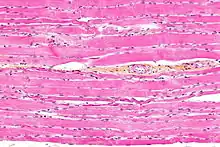

Micrograph showing skeletal striated muscle.

- Muscle tissue that appears striped under the microscope as a result of the myofibrils being organized into regular units (sarcomeres).